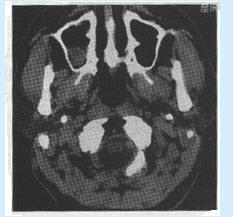

患者男,42岁。慢性鼻炎20余年。CT检查如图。诊断为()

A:右侧上颌窦慢性炎症

B:右侧上颌窦黏液囊肿

C:右侧上颌窦黏膜下囊肿

D:右侧上颌窦乳头状瘤

E:右侧上颌窦息肉